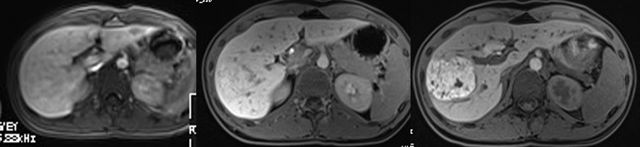

MRI表现(图2):T1WI等或稍低信号,T2WI呈等或稍高信号,中心纤维瘢痕呈高信号。增强扫描(图3)动脉期明显强化,门脉期强化程度逐渐下降,“瘢痕”则表现为延迟强化;

肝细胞期则为高摄取(具有诊断价值的特征性表现),“瘢痕”则为相对低摄取区(图4)。